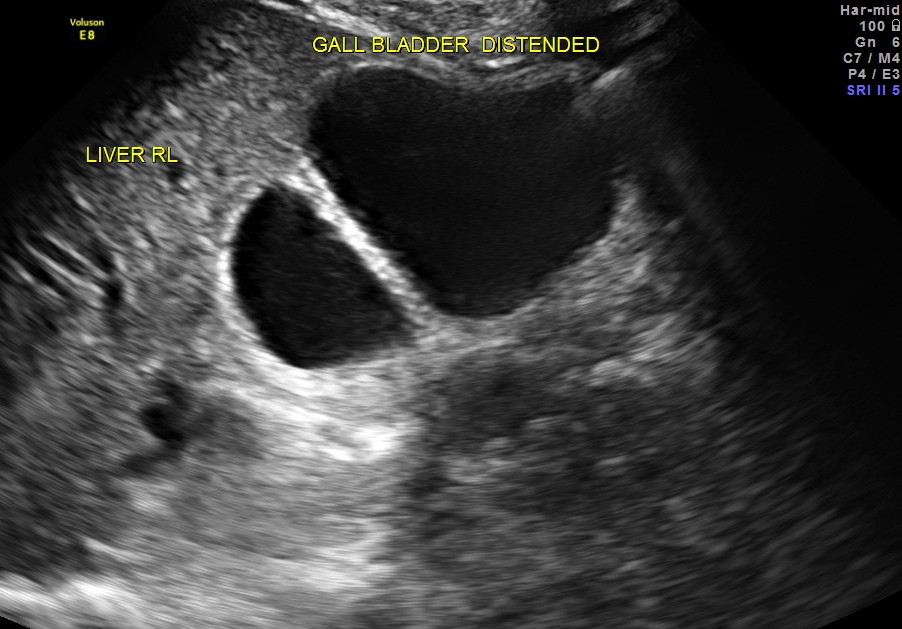

Courvoisier’s law (or Courvoisier syndrome, or Courvoisier’s sign or Courvoisier-Terrier’s sign) states that in the presence of an enlarged gallbladder which is nontender and accompanied with mild jaundice, the cause is unlikely to be gallstones. Usually, the term is used to describe the physical examination finding of the right-upper quadrant of the abdomen. This sign implicated possible malignancy of the gall bladder or pancreas and the swelling is unlikely due to gallstones.

This was a 55 year old man with history of jaundice and upper abdominal pain .